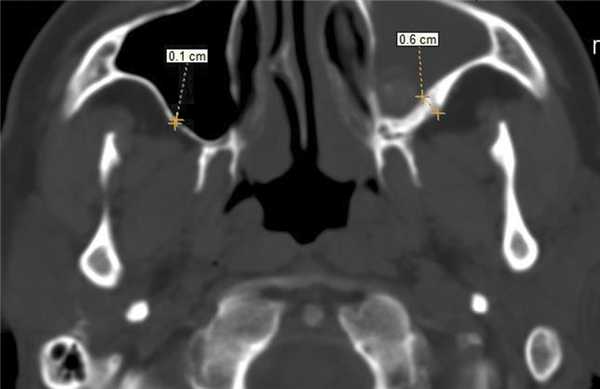

В костном режиме программы просмотра изображений утолщение костных стенок верхнечелюстной пазухи определялось в 21% случаев (рис. 2, 3), что указывает на хронический характер воспаления. «Оптический эффект» в мягкотканном режиме программы просмотра диагностических изображений определялся у 30,7% больных, что указывает на вовлечение надкостницы.

Рис. 2. Рентгеновская компьютерная томограмма околоносовых пазух. Аксиальная проекция, костное окно.